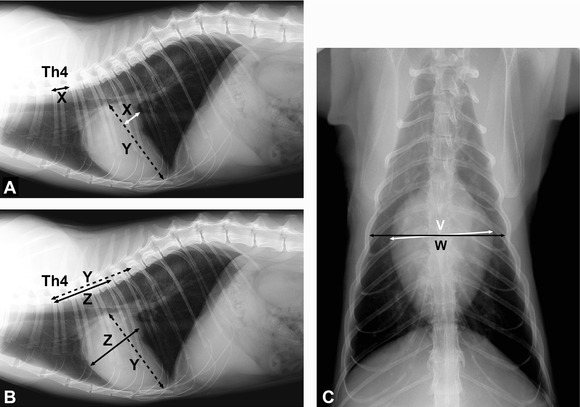

Обнаружив сердечные шумы и нарушения ритма, ветеринарный специалист, как правило, назначает рентгенологическое исследование грудной клетки, электрокардиографию и эхокардиографию сердца.

Рентгенологическое обследование позволяет обнаружить не только увеличение левого желудочка и предсердия, но и выявить плевральный выпот. ЭКГ сердца выявляет нарушения в его работе у 70% больных гипертрофической кардиомиопатией кошек.

Рентгенограмма (боковая и прямая проекция) кошки с ГКМП